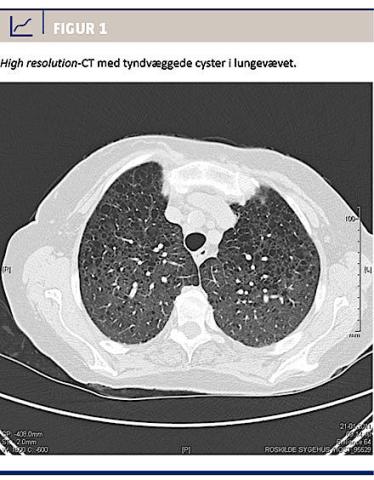

En 75-årig kvinde blev henvist til en lungemedicinsk afdeling til udredning af langvarig dyspnø, der ikke responderede på inhalationssteroid. Hun havde aldrig røget eller været udsat for passiv rygning, asbest eller andre kendte patogener. Som 33-årig og 35-årig gennemgik hun to graviditeter, hvoraf den første var kompliceret af præeklampsi, men ikke dyspnø. Hun havde aldrig været i hormonbehandling og havde ingen neurologiske symptomer i anamnesen, heller ikke krampeanfald, og der var ingen kognitive deficit, der kunne tyde på tuberøs sklerose. Som 47-årig var hun indlagt pga. dyspnø, recidiverende kylothorax og pleuraempyem. Behandlingen bestod i pleuracentese og antibiotika, og patienten angav, at lungehinderne blev »klistret sammen« ved injektion af et ukendt stof. Man fremkom ikke med en diagnose. Hendes behandling blev afsluttet efter fire års ambulant opfølgning uden medicinsk behandling, og uden at der i øvrigt var noget at bemærke. Hun oplevede fortsat let aktivitetsdyspnø, der blev mere udtalt ved 70-årsalderen. På baggrund af spirometri med obstruktivt præg forsøgte patientens egen læge behandling med inhalationspræparater, hvilket dog var uden større effekt. I en alder af 74 år fik patienten en formodet behandlingsrefraktær (penicillinbehandlet) pneumoni, som førte til indlæggelse. Ved en røntgenundersøgelse af thorax sås øget retikulær tegning, hvorfor der blev foretaget HRCT, som viste udbredt affektion af lungevævet med multiple, tyndvæggede, runde cyster af varierende størrelse bilateralt (Figur 1) foruden mediastinal og retrokrural adenopati og venstresidig pleuraeffusion, hvilket var foreneligt med LAM. Alfa-1-antitrypsinniveauet var upåfaldende. Fjorten måneder senere foretog man PET-CT pga. et nytilkommet suspekt infiltrat, som ved røntgenundersøgelse af thorax var set på højre lunge. Mistanken om lungetumor blev frafaldet, men der fandtes en 1 × 1 cm uspecifik proces i venstre nyre samt flere små processer i gl. thyroidea – alle uden fluordeoxyglucoseoptagelse. Ved en objektiv undersøgelse af huden var der ingen tegn på tuberøs sklerose (negle- eller hudforandringer). Der blev foretaget finnålsaspirat af den største proces i gl. thyroidea. Aspiratet viste, at der var tale om et benignt adenom. Processen i nyren fremtrådte radiologisk ikke som et angiomyolipom. Ud fra størrelse og udseende vurderede man fra urologisk side, at watchful waiting med årlig ultralydskanning var tilstrækkelig. I forløbet fik patienten konstateret svær pulmunal hypertension, dilateret højre ventrikel med normal uddrivningsfraktion og atrieflimren. Der blev påbegyndt behandling med marevan, enalapril, furosemid og verapamil med god symptomatisk effekt, og pleuravæsken forsvandt.